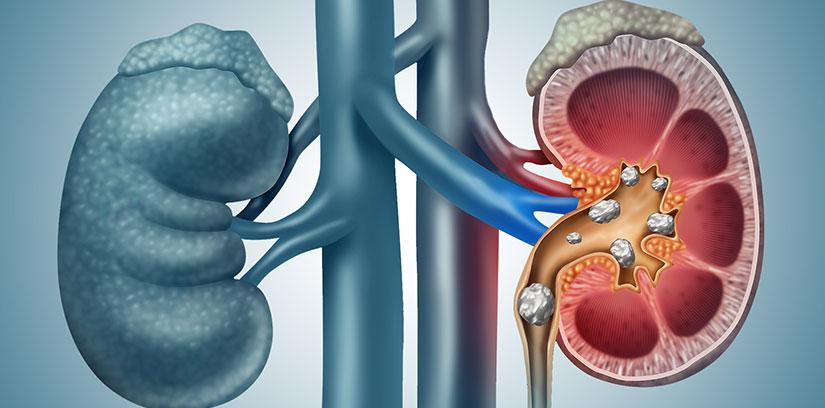

Anyone who has experienced a kidney stone will tell you it’s a pain they never want to feel again. While factors like genetics play a role, many people are surprised to learn that their everyday routine is often the main culprit behind this excruciating condition.

Chronic dehydration is the single biggest risk factor for kidney stones. When you don’t drink enough fluids, your urine becomes highly concentrated. This allows minerals and salts to easily clump together and crystallize into stones. Furthermore, if you regularly do heavy workouts, hot yoga, or spend time outside in the heat, you are losing significant water through sweat, leaving less fluid to flush out your kidneys.

It sounds entirely counterintuitive: since most kidney stones are made of calcium, shouldn’t you avoid calcium-rich foods? Actually, doing so increases your risk! When your diet is low in dietary calcium, your body absorbs higher levels of oxalates (stone-forming compounds) in your intestines. These oxalates then travel to your kidneys, where they form stones.

Oxalates are naturally occurring compounds found in many incredibly healthy foods, including spinach, beets, nuts, sweet potatoes, and dark chocolate. While you shouldn’t ban these from your diet, eating them in large quantities on their own can lead to calcium oxalate stones.

Adjusting your diet is the best way to prevent future kidney stones, but drinking water and changing your meals simply cannot dissolve a stone that has already grown too large or become lodged in your urinary tract. If you are experiencing severe waves of pain in your back or abdomen, nausea, or painful urination, you need professional medical intervention.